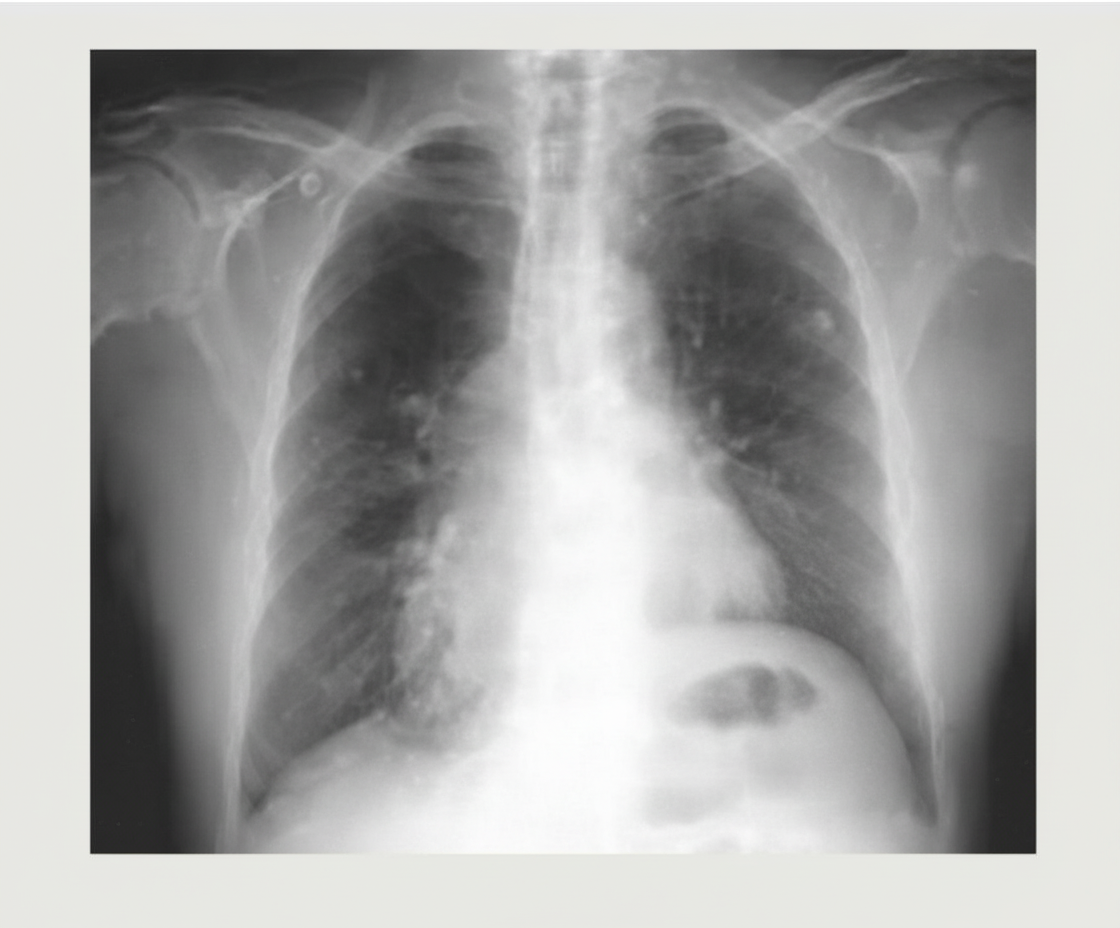

A 32-year-old male who underwent a lung transplant 1 year ago, with a history of acute rejection requiring increased immunosuppression, now presents with low-grade fever, generalized fatigue, and weight loss. Chest x-rays are obtained. What is the most likely diagnosis?

Explanation: ***Posttransplant lymphoproliferative disorder (PTLD)*** - **PTLD** is strongly associated with **EBV reactivation** in immunocompromised transplant recipients, especially those with **increased immunosuppression** following acute rejection episodes. - Presents with **constitutional B-symptoms** (fever, fatigue, weight loss) and typically shows **pulmonary nodules or masses** on chest imaging in lung transplant patients. *Squamous cell carcinoma* - While transplant recipients have **increased malignancy risk**, squamous cell carcinoma typically develops **years to decades** post-transplant, not within 1 year. - Usually presents as **localized skin lesions** or **bronchial masses**, not with generalized constitutional symptoms and systemic involvement. *Aspergilloma* - Represents a **fungal ball** within pre-existing **pulmonary cavities** and typically occurs in patients with underlying lung disease like **tuberculosis** or **sarcoidosis**. - Presents with **hemoptysis** and **productive cough**, not constitutional symptoms, and appears as a **mobile mass within a cavity** on imaging. *Phantom tumor or pseudotumor* - Refers to **loculated pleural fluid** that mimics a mass on chest X-ray, commonly seen in **congestive heart failure** patients. - Represents **inflammatory fluid collection**, not a true neoplastic process, and would not cause systemic constitutional symptoms like fever and weight loss.